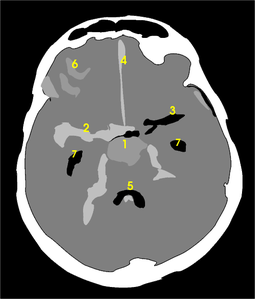

Subarachnoid hemorrhage CT.JPG Subarachnoid hemorrhage CT map.png

CT scan Graphic

The computed tomography image represents a section through the skull at the level of a hat brim, near the skull base. The front of the skull is shown at the top of the image and the right and left sides are interchanged. Therefore, for example, the structure numbered [2] is in the right hemisphere of the patient's brain.

The skull, shown in white, surrounds the brain. At the front, the frontal sinus is black.

The blood from the ruptured aneurysm [1] has spread to the surrounding cisterns (the cisterna valleculae cerebri [2], appears relatively clear, however, on the left-hand side [3]). The blood has spread far into the small subarachnoid space. Blood is evident in the interhemisphere fissure [4] and on the gyri [6] of the right hemisphere. There is also a hemorrhage in the fourth ventricle [5]. The lateral ventricles [7] are free of blood.